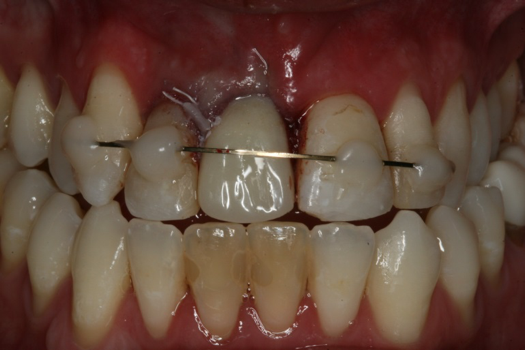

Case 3. TRAUMA: SINGLE Central INCISOR-GUIDED Smile

A 23-year-old man reported to the dental practice on January 3. Apparently, while on vacation and celebrating the New Year, the patient experienced a loss of equilibrium and found himself horizontal in the crosswalk. When surveying the damages, his friends noticed he was missing tooth No. 8. Those who were involved were not able to find the missing maxillary central incisor. The young man was eventually seen about 3 days after the trauma. A CBCT radiograph, study models, and photographs were collected, and teeth Nos. 6 through 10 were immobilized with composite and 20 x 20 orthodontic wire (Figure 14). The CBCT and photos were emailed to the dental laboratory, and the analog intraoral impression with a centric occlusion bite registration was sent via ground transportation. Due to the nature of the trauma, the laboratory and the author expeditiously converted the analog diagnostics and merged all the patient's data sets to develop the plan. Based on the 3D data sets, the laboratory and the dentist were able to accurately assess the volume of bone and soft tissue remaining after the trauma. The volume was still intact and soft tissue was plentiful (Figure 15 and Figure 16).

The decision was to develop a surgical guide, place the implant, and fabricate a screw-retained one-piece non-engaging abutment with a slender emergence profile and a polymethyl methacrylate (PMMA) provisional. Ten days after the trauma, the patient was seen in the dental office for the placement of the dental implant. On the day of surgery, a 3D-printed surgical guide was used, developed from the CBCT radiograph and the digitized impressions (Figure 17 and Figure 18).

Fig 14. Immobilization splint placed 3 days after trauma.

Figure 14